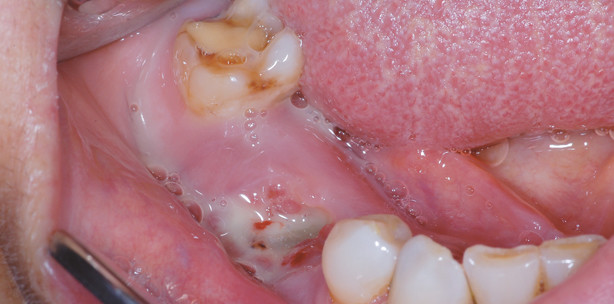

Bisphosphonate werden bei benignen Knochenstoffwechselstörungen, dem multiplen Myelom und ossären Metastasen solider Tumore verabreicht. Alleine in Deutschland leiden zwischen 8 und 10 Millionen Menschen unter Osteoporose, und jährlich werden je etwa 60.000 Neuerkrankungen für das Brust- und das Prostatakarzinom gemeldet.8 Von den vielen unterschiedlichen Definitionen hat sich die der American Association of Oral and Maxillofacial Surgeons (AAOMS) durchgesetzt. Diese beschreibt die BP-ONJ rein klinisch als eine enoral freiliegende Knochennekrose, die über einen Zeitraum von mindestens acht Wochen bestehen muss, bei vorausgegangener oder aktueller Bisphosphonatmedikation, ohne dass eine Kopf-Hals-Radiatio hat vorliegen dürfen.9 Aber schon hier gibt es Kritikpunkte, ob eine Radiatio eine BP-ONJ ausschließt oder hier nicht vielmehr eine besondere Risikokonstellation vorliegt10, zumal auch histologisch Unterschiede zwischen der Osteoradionekrose und der BP-ONJ bestehen können.11 Ebenfalls nach der AAOMS wird die BP-ONJ in unterschiedliche Stadien eingeteilt (Abb. 1–3). Neben der prinzipiell mit einem Risiko behafteten Gruppe von Patienten, die Bisphosphonate zu sich nehmen, beschreibt das Stadium 0 Patienten mit Bestehen von nichtspezifischen Symptomen, ohne dass klinisch eine Nekrose verifiziert werden kann. Im Stadium I liegt symptomlos enoral nekrotischer Knochen vor, der im Stadium II mit Schmerzen und entzündlichen Veränderungen zusätzlich symptomatisch wird. Im Stadium III gibt es zusätzliche Komplikationen wie ausgedehnte Osteolysen, eine Beteiligung der Kieferhöhlen, pathologische Frakturen oder auch Fistelungen nach extraoral.9

Die Früherkennung der BP-ONJ wird am besten durch die klinische Inspektion gewährleistet, wohingegen bildgebende Verfahren in den Hintergrund rücken.8 Allerdings kann man bereits an der Panoramaschichtaufnahme bei Patienten, die unter Bisphosphonattherapie stehen, entsprechende Veränderungen sehen (Abb. 4). Die Untersuchung von Knochenstoffwechselmarkern wird in der Literatur kontrovers diskutiert, sodass hier abschließend noch keine Empfehlung ausgesprochen werden kann.8 Die Idee dahinter ist, dass aufgrund der eingeschränkten Funktion der Osteoklasten, diese weniger Knochen abbauen und daher auch weniger Knochenabbauprodukte im Blut zu finden sind. Die Menge an diesen Abbauprodukten wird dann in einem zweiten Schritt mit dem Risiko der Entstehung einer BP-ONJ korreliert. Je höher die Konzentration im Blut, desto geringer das Risiko der Entstehung einer BP-ONJ.20 In Abhängigkeit vom Stadium werden therapeutisch durch die AAOMS zunächst nur symptomatische Therapieregime empfohlen. Im Stadium II werden oberflächliche Debridements empfohlen, um den ständigen Reiz auf die Weichgewebe zu nehmen. Erst im Stadium III empfiehlt die AAOMS die chirurgische Intervention im Sinne der Nekrosenabtragung.9 Die deutschen Leitlinien grenzen sich hier ab, da sie bei abwartendem Verhalten eine asymptomatische Progredienz der Nekrose erwarten und empfehlen bereits in früheren Stadien eine chirurgische Intervention.8 Die Leitlinie der AAOMS datiert aus dem Jahr 2009, die deutsche Leitlinie aus dem Jahr 2012 und bezieht sich somit auch auf aktuellere Literatur, die sich dahingehend verdichtet, dass man immer früher chirurgisch interveniert.